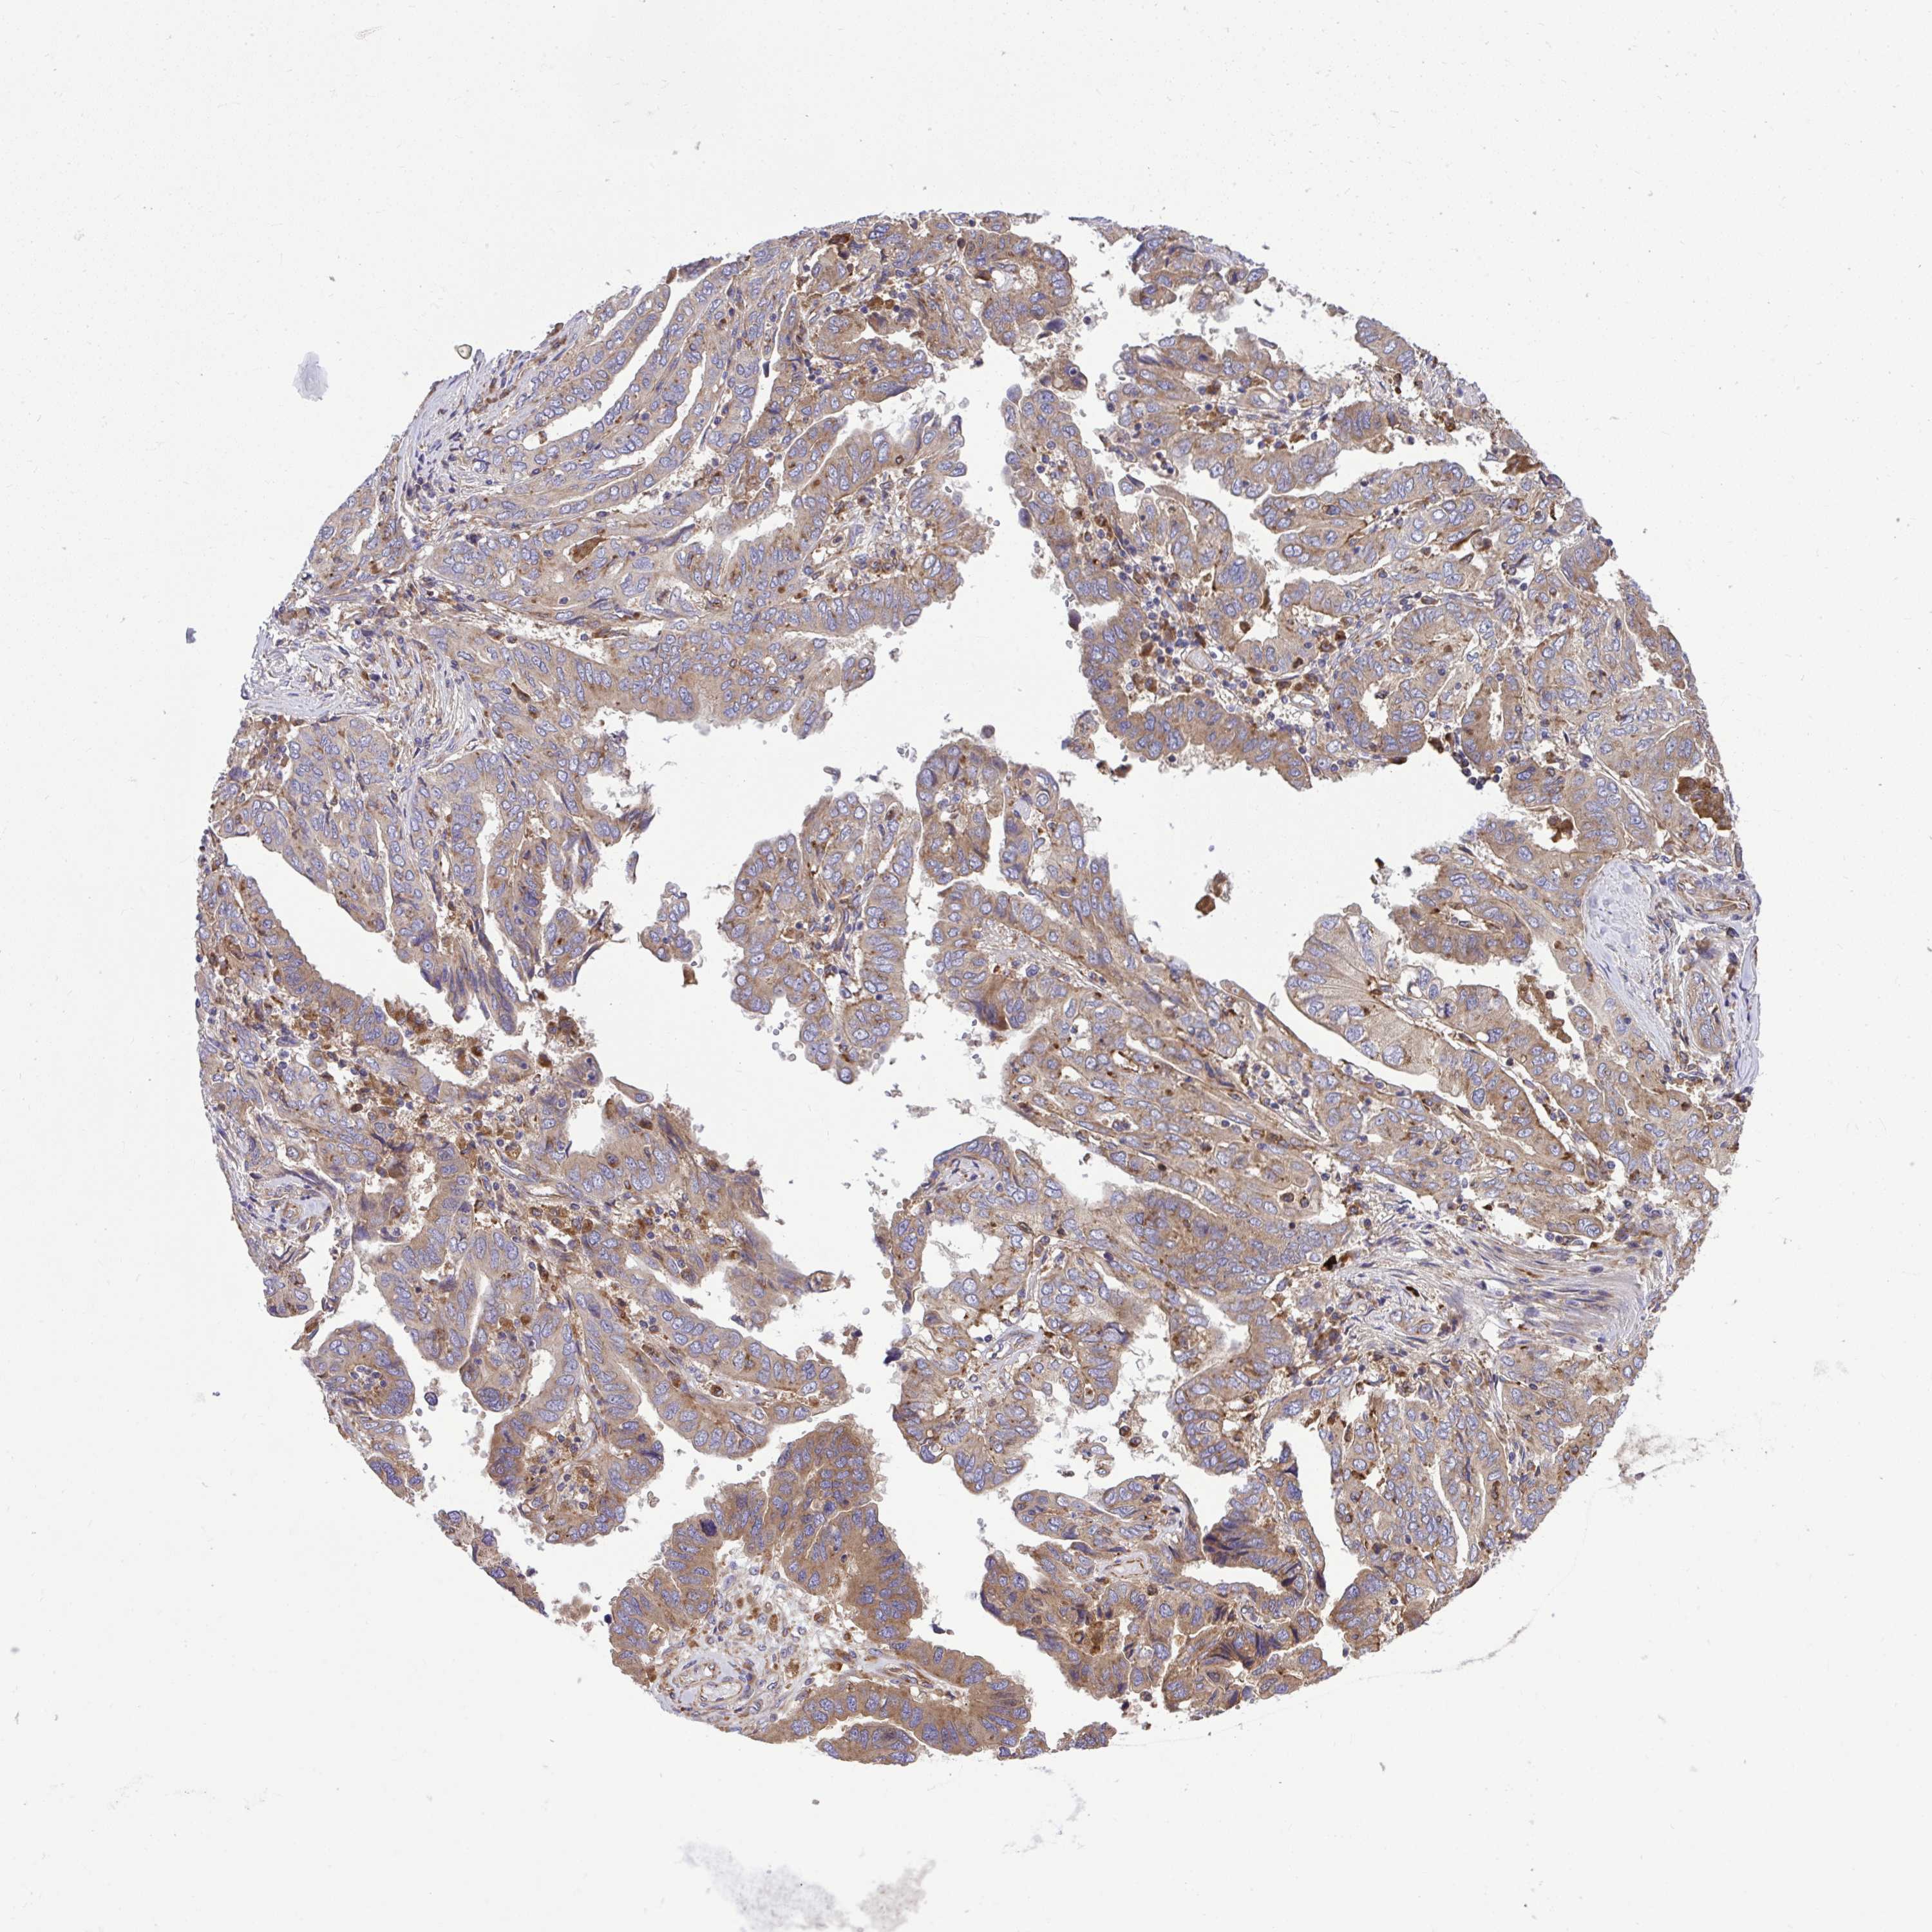

OVARIAN CANCER - Protein expressioni

A mouse-over function shows sample information and annotation data. Click on an image to view it in a full screen mode. Samples can be filtered based on level of antibody staining by selecting one or several of the following categories: high, medium, low and not detected. The assay and annotation is described here.

Note that samples used for immunohistochemistry by the Human Protein Atlas do not correspond to samples in the TCGA dataset.

Antibody stainingi

Antibody staining in the annotated cell types in the current human tissue is reported as not detected, low, medium, or high, based on conventional immunohistochemistry profiling in selected tissues. This score is based on the combination of the staining intensity and fraction of stained cells.

Each image is clickable and will lead to virtual microscopy that enables deeper exploration of all samples and also displays staining intensity scores, fraction scores and subcellular localization as well as patient and tissue information for each sample.

Antibody HPA035945

Antibody HPA056766

Antibody CAB037212

Staining

High

Medium

Low

Not detected

Cystadenocarcinoma, serous, NOS

Carcinoma, endometroid

Cystadenocarcinoma, mucinous, NOS

Carcinoma, NOS